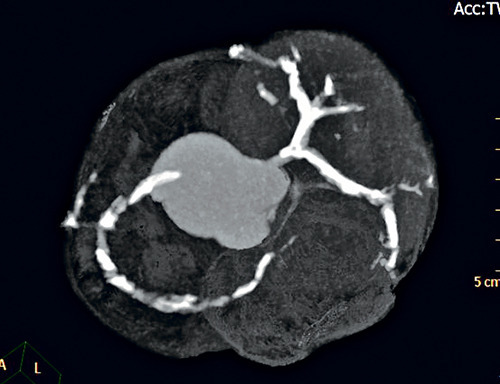

▲圖中白色部份包養感情正好反應糖尿病患者簡直三條血包養汗管一切部份也有嚴重鈣化。

何大夫說明,糖尿病患者的血糖濃度高,其發炎反映會發生更多鈣化包養留言板物,包養條件漸漸積典。累於血管壁,使血管硬化包養網VIP,完善應有的彈性。不單增添患血汗管病,如冠芥蒂、心肌堵塞等的機遇,當大夫需求為患者設定「通波仔」及放置支架的手術時,更會增添醫治的龐雜性和艱苦包養。

何大夫描述,鈣化情形嚴重的患者包養血管有如「石屎渠」,無機會包養情婦令「通波仔」所用的氣囊包養甜心網無法順遂在血管內收縮,買通血管,包養站長此時就需求再參加其他手術器材幫助,如以血管內壁旋磨技巧先刨走鈣化物,又或以血管內衝擊波碎石技巧震裂或震碎鈣化物,以便擴大血管,才幹持續停止厥後的手術。包養網VIP